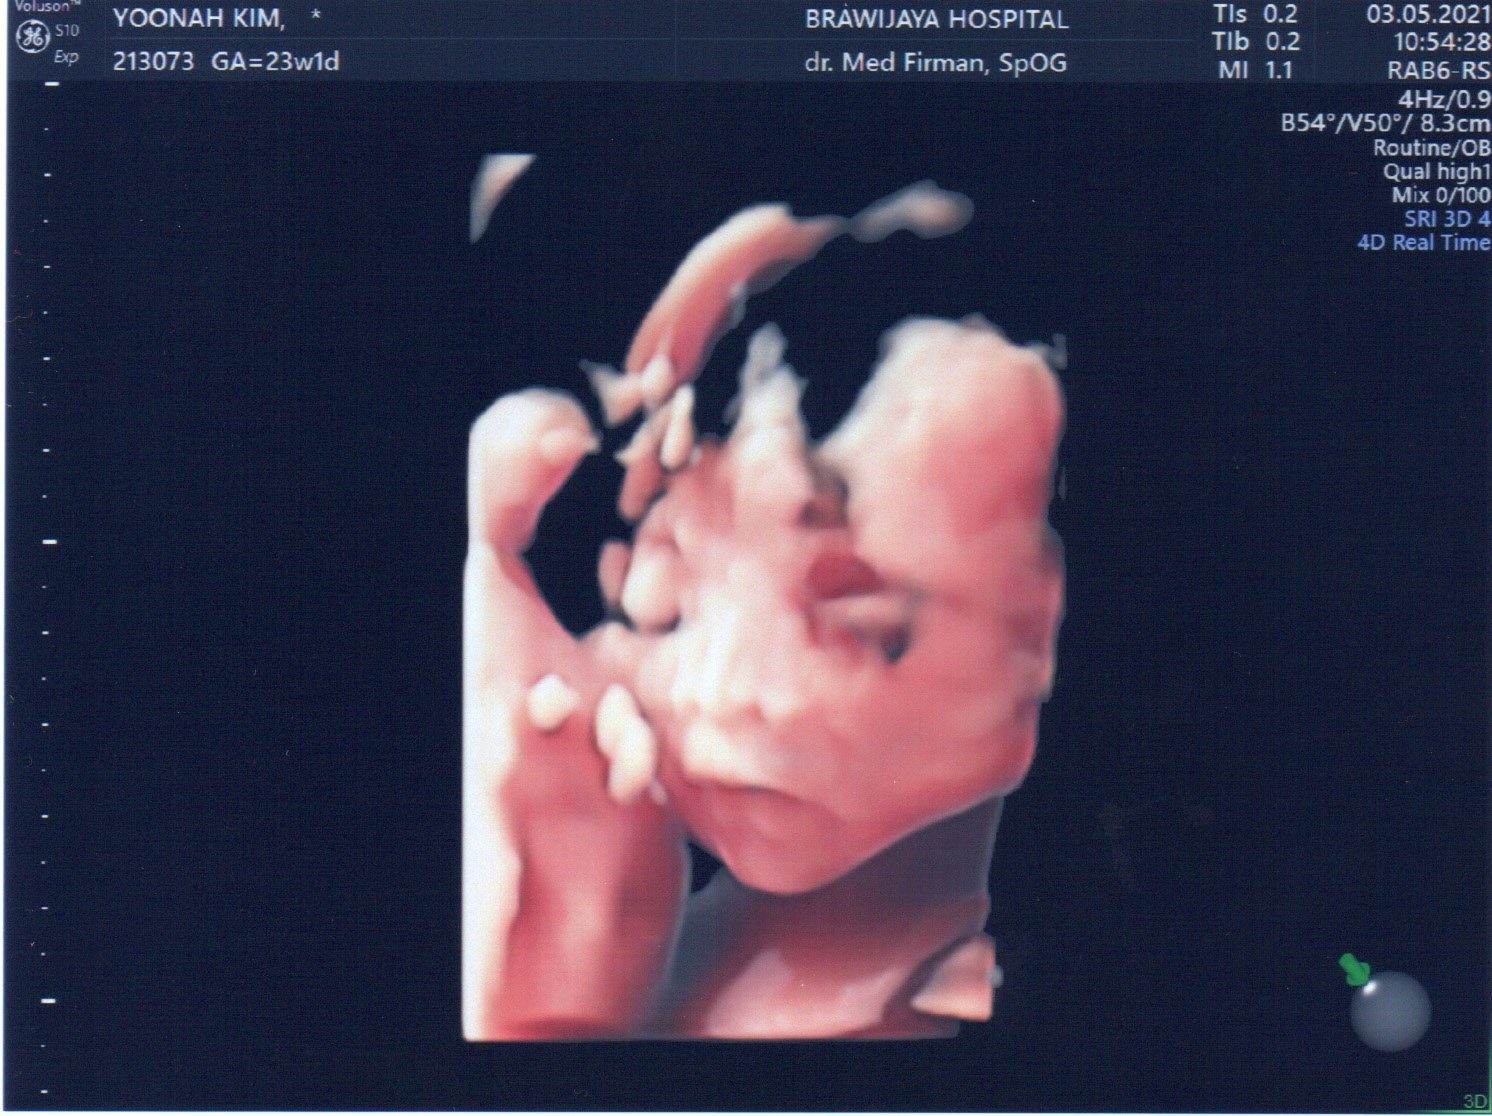

23주만에 드디어 얼굴을 보여주신 울 아드님...

집사람은 코가 낮은 거 같다고 걱정한다. ㅎㅎㅎ

설사 코가 낮다고 하더라도 코가 자랄 시간은 아직 많이 남았다구~~!!